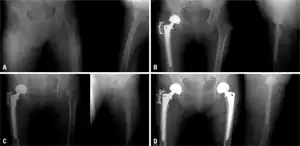

-

a) Initial radiographs of intertrochanteric fracture b) postoperative - bipolar hemiarthroplasty c) subsequent fracture in left femur neck d) radiograph after a bipolar hemiarthroplasty, the individual began medication for osteoporosis -

Conventional radiography is useful, both by itself and in conjunction with CT or MRI, for detecting complications of osteopenia (reduced bone mass; pre-osteoporosis), such as fractures; for differential diagnosis of osteopenia; or for follow-up examinations in specific clinical settings, such as soft tissue calcifications, secondary hyperparathyroidism, or osteomalacia in renal osteodystrophy. However, radiography is relatively insensitive to detection of early disease and requires a substantial amount of bone loss (about 30%) to be apparent on X-ray images.

The main radiographic features of generalized osteoporosis are cortical thinning and increased radiolucency. Frequent complications of osteoporosis are vertebral fractures for which spinal radiography can help considerably in diagnosis and follow-up. Vertebral height measurements can objectively be made using plain-film X-rays by using several methods such as height loss together with area reduction, particularly when looking at vertical deformity in T4-L4, or by determining a spinal fracture index that takes into account the number of vertebrae involved. Involvement of multiple vertebral bodies leads to kyphosis of the thoracic spine, leading to what is known as dowager's hump.